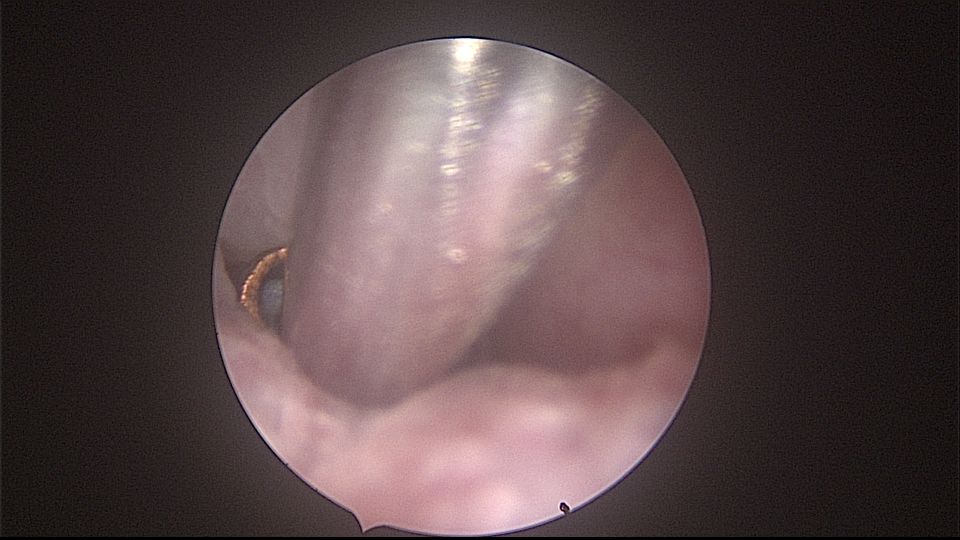

患者52岁,G2P1,顺产1次。安环27年,外院取环失败。病人肥胖,B超提示子宫前位,节育环距宫底0.9cm。子宫极度前倾前屈位,宫腔镜见宫颈管组织杂乱,宫颈管上段右前壁见假道,膨宫不良,视野模糊,寻找宫腔方向困难,准备B超监护过程中,拆走扩阴器,腹部下压子宫,终于寻找到了宫颈内口,看到了爱母环下端,异物钳牵拉出节育环,再次探查宫腔,无其他异常。